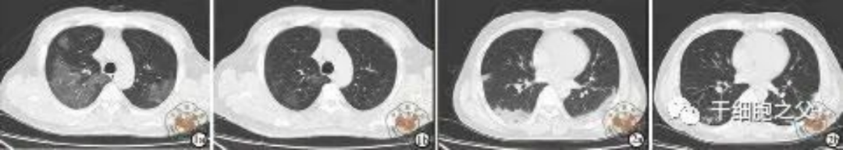

與安慰劑組相比,人臍帶間充質(zhì)干細(xì)胞修復(fù)組全肺病變體積改善了10.8%,并且人臍帶間充質(zhì)干細(xì)胞修復(fù)組在每一個隨訪節(jié)點(diǎn)都顯示出固體組分病變體積比例減少。此外,人臍帶間充質(zhì)干細(xì)胞組有17.9%的患者在12個月時CT圖像變?yōu)檎#参縿┙M沒有。